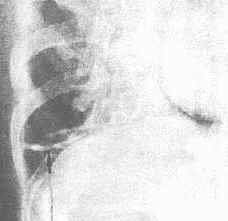

膈上肺野外帶兩條橫行條狀影膈上肺野外帶兩條橫行條狀影

多見了一側或兩側肺野底部。這種肺不張大多是由於該部分肺野呼吸運動障礙,橫隔運動減弱有關。多見於一則或兩側肺底部,膈頂上方,長約2-6cm扁長條形、橫行密影,邊緣較模糊,在正側位上都可見到,往往可達胸膜面,但從不穿過葉間裂。

盤狀肺不張,指亞段以上的肺不張,多位於膈頂上方,約2-6cm長,扁平條狀陰影,外端達胸膜表面,不穿過葉間裂。